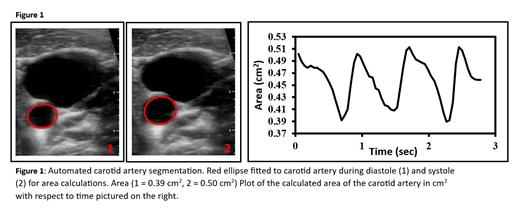

All participants had their vitals taken and their right common carotid artery imaged in supine position following at least 10 minutes rest. Imaging was performed by an experienced imaging professional (AB, 10 years experience) using a Butterfly IQ + ultrasound probe (Burlington, MA) and an Apple smartphone (Cupertino, CA) in the B-mode vascular setting. Three to ten second recordings of the carotid artery were recorded at a rate of approximately 20 frames per second. In house MATLAB scripts were developed for semiautomated cross sectional area segmentation across the cardiac cycle to calculate vessel lumen area (Figure 1). Strain was calculated using the ratio of change in systolic and diastolic area over diastolic area, and distensibility (1/stiffness) was calculated as strain/ln[SBP/DBP] (Godia, 2007). Univariate and stepwise multiple analysis was performed to determine the correlates of arterial distensibility.